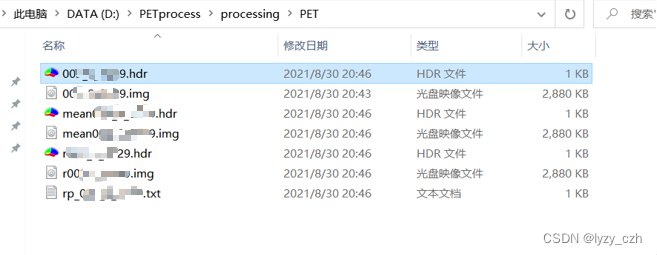

此时在输出目录下生成如下文件: